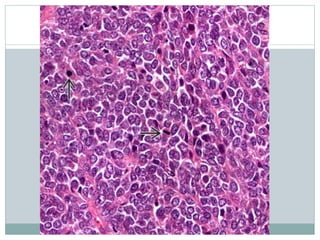

Cells  Uniform cells Rarely spindled  Scant cytoplasm with indistinct membranes  Clear from glycogen  Fine chromatin, inconspicuous nucleoli  Atypical (large cell) variant  Large nuclei, conspicuous nucleoli, pleomorphism, spindling

• #11 Ewing sarcoma (ES) is a highly cellular, high-grade sarcoma with a dense, solid to sheet-like distribution of cells, as depicted. Most tumors are diagnosed on small biopsy prior to treatment with chemotherapy, and large, preserved sections, as shown, are uncommon.

• #12 The tumor is classically very cellular cells arranged in diffuse sheets or lobules. Tumor cells and nuclei are generally uniform. Stromal vessels are commonly found.

• #18 Tumor cells in ES are generally very uniform, and overlapping of nuclei is quite common. Chromatin is finely and evenly distributed, and nucleoli are small, if present.

• #19 This high-power H&E of ES shows a sheet of neoplastic cells with no particular pattern. The cells are medium sized and have a high nuclear:cytoplasmic ratio. The nuclear chromatin is evenly distributed, and there are numerous mitotic figures in this example.